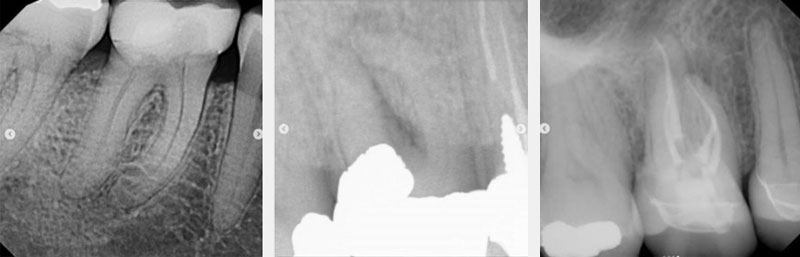

We’ve all had the same patient in the chair, whether you’re a general practitioner or an endodontist. A molar was prepped and temped uneventfully a few weeks or months ago (Figs. 1–3). The patient presents for the crown delivery appointment, and the rest can vary.

Sometimes the crown was just cemented and placed after being prepped and temped uneventfully, and the patient never reported any symptoms or discomfort (see Figs. 4–6). Often during crown treatment planning, (newer) PAs are not taken, and the crown gets prepped and temped based on the FMX from years earlier.

So, the crown was prepped and temped based on the previous year’s recent BW (often taken every two years). Unknowingly, without a “recent” PA, periapical pathology likely existed even before the crown was prepped and temporized.